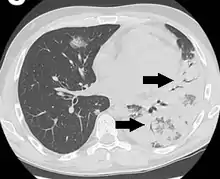

An air bronchogram is defined as a pattern of air-filled bronchi on a background of airless lung.[1]

In pulmonary consolidations and infiltrates, air bronchograms are most commonly caused by pneumonia or pulmonary edema (especially with alveolar edema).[2][3]

Lung nodules

For lung nodules, air bronchograms used to be associated with infectious causes of consolidation and, therefore to be benign. However, in the setting of a lung nodule, an air bronchogram is actually more frequent in malignant than in benign nodules.[1][4] studied the tumour-bronchus relationship and described five types:[1]

Keeping in mind how a tumour with lepidic growth expands, it is not surprising that the air bronchogram in these tumours is smooth. In contradistinction, a desmoplastic response may cause irregularities of the bronchogram.[1] When retraction of tumoural fibrosis occur, the air bronchogram can even become somewhat dilated. Although this sign can occur in all lung cancer cell types, it is more common in adenocarcinoma.[1] Studies suggest the association of this sign with an activated epidermal growth factor receptor (EGFR) mutation.[1]